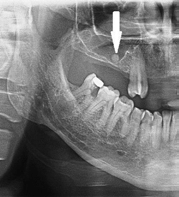

1. What condition can be seen in the following X ray? ( solid arrow)

the calcification within Stensen's duct of parotid